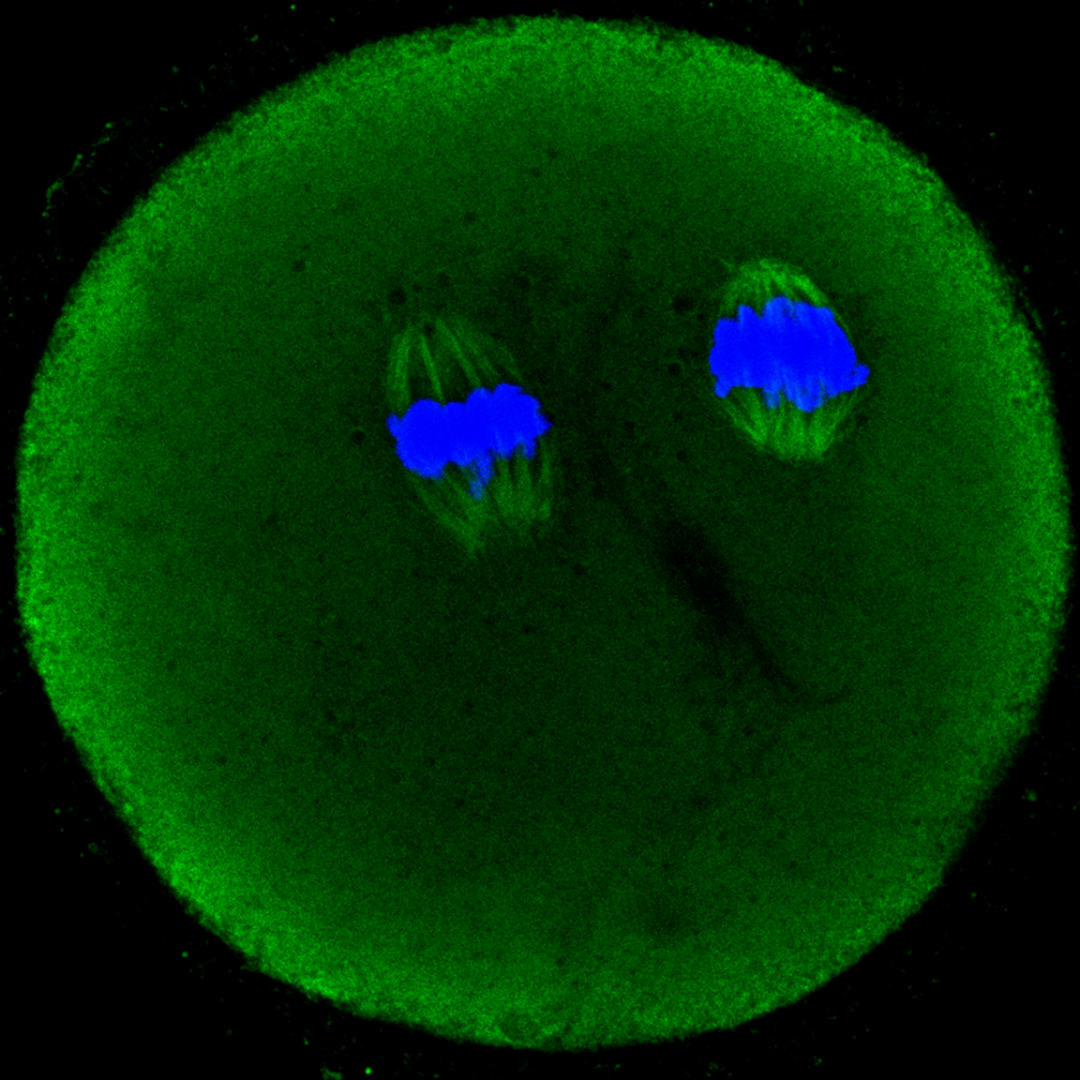

《Trick or Treat?》

肖晨语 (公共卫生学院 22级公共卫生与预防医学专业研究生)

本图为通过免疫荧光染色的小鼠卵母细胞,绿色是纺锤丝,蓝色是DAPI。两簇纺锤丝包绕的细胞核,配合黑色的背景,像极了夜色里的南瓜灯。正如我们的科研生活,是重复不出的实验结果亦或是不经意间的惊喜发现,trick or treat ?无论结果如何,都是研究生涯中至关重要的一步。